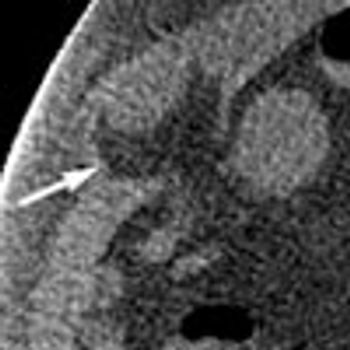

Acute abdominal pain, fever, and chills prompted a 51-year-old man to visit his local hospital twice in one week. On both visits, a clinical and laboratory workup was negative. He then presented to a tertiary care center with worsening symptoms. His history included hypertension and tobacco and alcohol use.